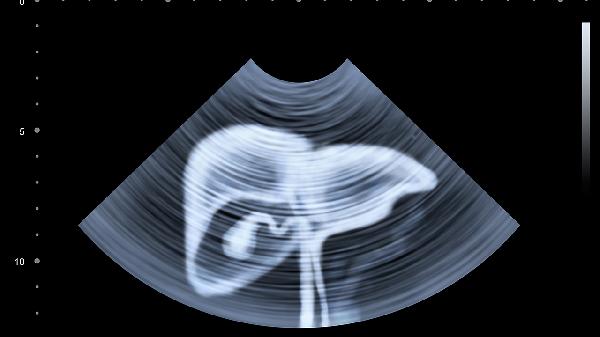

3、肝功能检查:

血清转氨酶检测可反映肝细胞损伤程度,丙肝患者常见ALT和AST轻度至中度升高。但约30%感染者肝功能指标可能正常,需结合其他检查。持续肝功能异常者需进一步评估肝纤维化程度,可通过弹性成像或血清学模型进行无创评估。